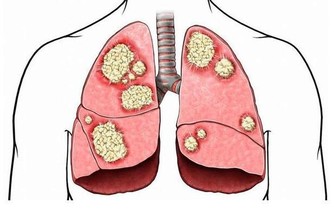

如此循環,血糖控制越來越差,飢餓感越來越重,終有一天會出現嚴重的並發症。